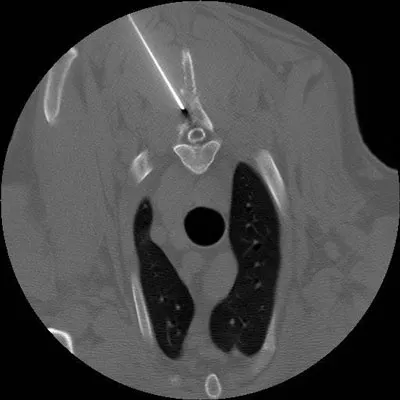

Note that if a mass on an internal organ or an internal lesion can be felt, it can be aspirated. However, for lesions that cannot be palpated, or for lesions near critical structures, such as major blood vessels, ultrasonography or computed tomography (CT) can be useful for guiding FNA (Figure 1).

CT-guided aspirate of a region of bony lysis within a dorsal spinous process; cytology revealed a sarcoma